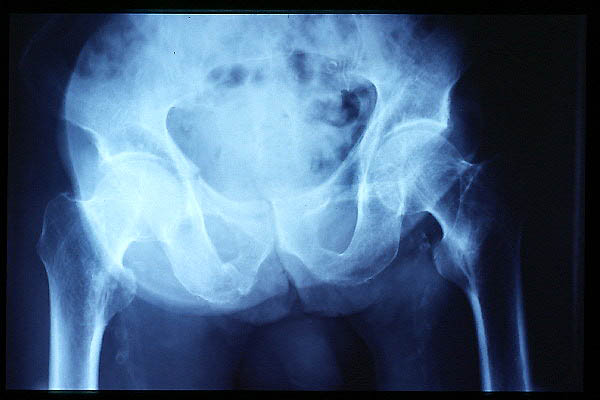

E de Paget